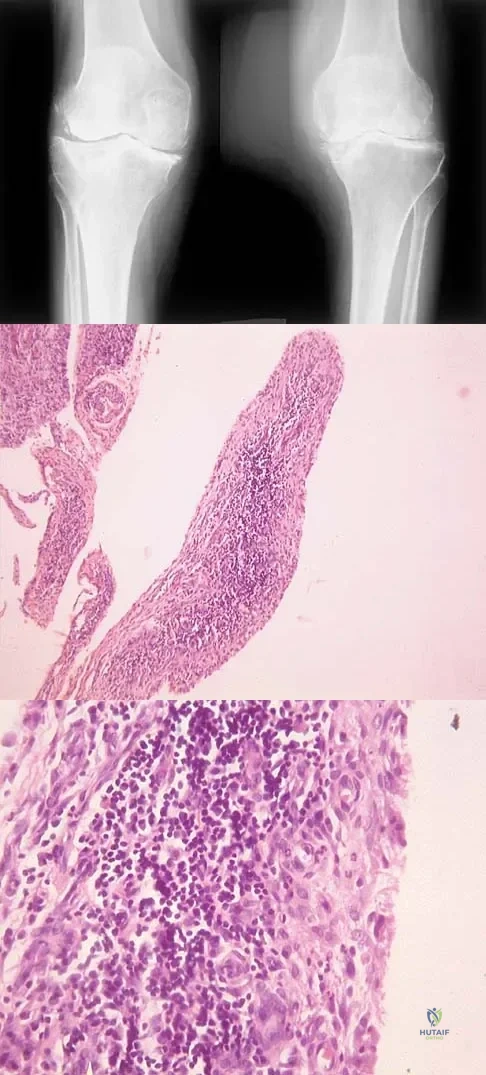

A 12-year-old girl has had progressive left knee pain for the past 4 months. She reports that the pain is unrelated to activity, and she has no history of fever or recent infections. Examination reveals full range of motion of the knee but tenderness along the medial joint line. Plain radiographs and MRI scans are shown in Figures 39a through 39d. A biopsy specimen of the lesion is shown in Figure 39e. Treatment should include

Explanation